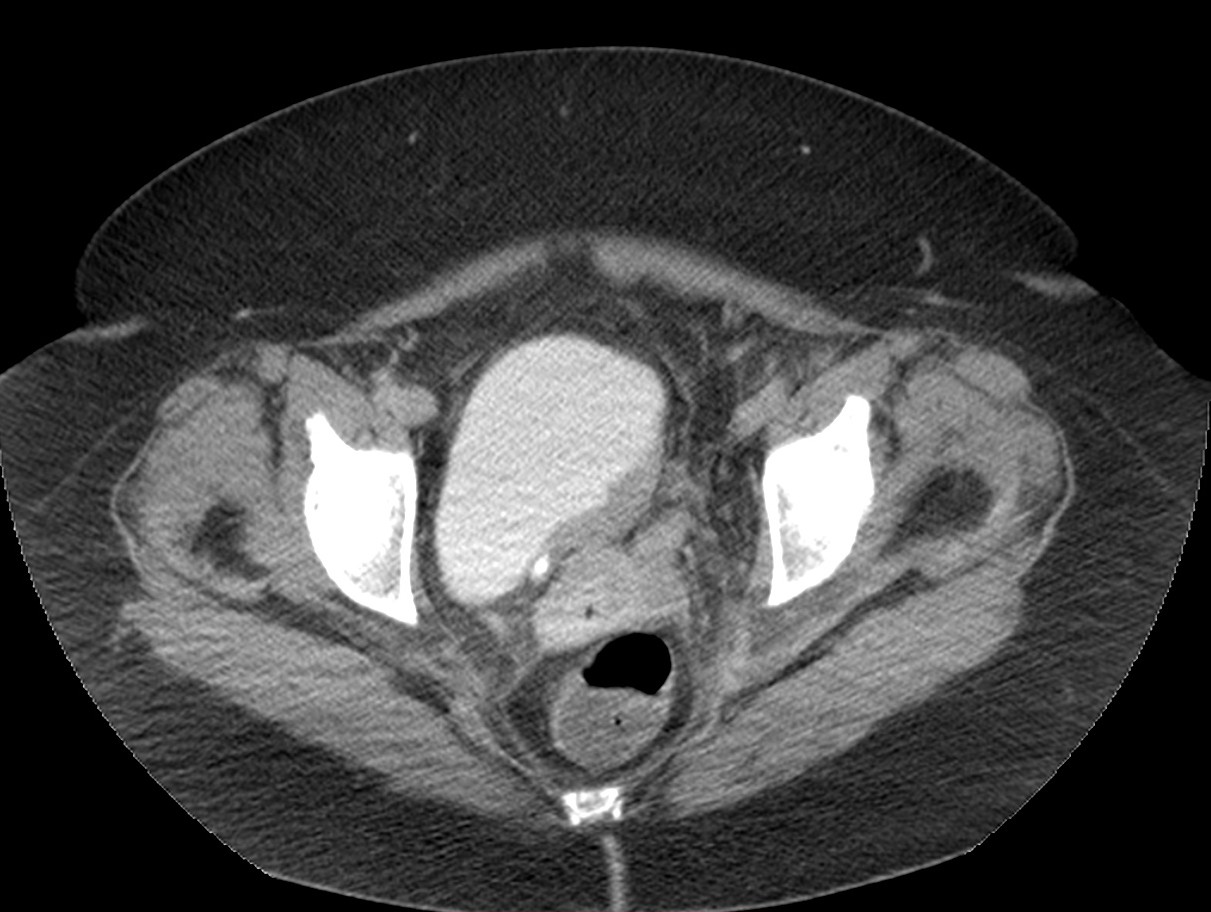

Paciente de 63 años, fumador que presenta hematuria macroscópica desde hace 10 días.

Ante dicho hallazgo se proceden a realizar estudios de imagen complementarios.

CASO CLÍNICO: Recopilatoción.

Paciente de 59 años con antecedentes personales de Cá de vejiga.

Se le realiza una Uro-Tc por seguimiento al año, aunque en esta ocasión el paciente refiere episodio de hematuria.